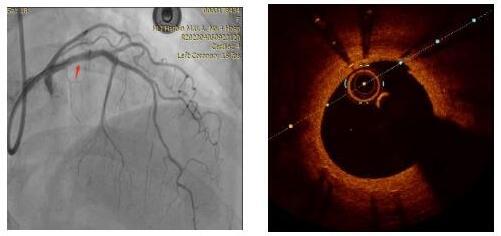

患者为62岁女性,是一位冠状动脉支架术后7年的患者,造影发现该患者冠状动脉前降支支架近端有大约80%的再狭窄,于是采用OCT检查对支架内情况进行测量,发现病变处有严重的狭窄。

对冠状动脉造影及OCT图像进行综合判断,目前已经具备安全进行冠状动脉内激光消蚀的条件,于是在病变处进行激光消融,随后在OCT指导下采用后扩球囊改善贴壁情况,顺利完成手术。